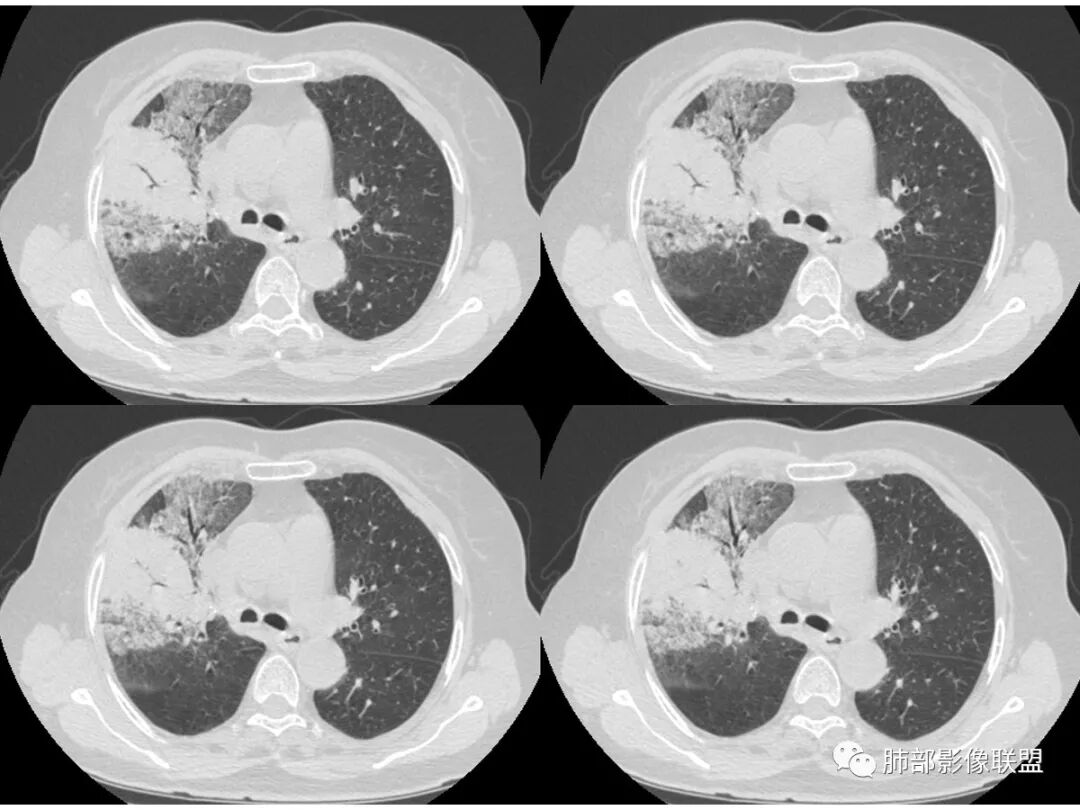

老年女性,右肺上叶大片实变及磨玻璃密度影,磨玻璃边缘清晰,内可见小叶间隔增厚,内可见空洞,似可见分隔,叶间裂局部膨隆,纵膈窗,没有增强,枯树枝不明显,肺炎型肺癌可能,鉴别大叶性肺炎,结核?

胸CT:右肺上叶实变内可见支气管充气征,近端支气管狭窄,远端扩张,周围可见毛玻璃影,右肺中叶支气管闭塞,并可见气道壁钙化,右肺中叶体积缩小,实变内可见空洞,并可见气液平面,空洞周围可见毛玻璃样影,右肺下叶支气管开口狭窄,右肺门淋巴结肿大。纵隔窗可见病灶与壁层胸膜间隙增宽,考虑良性病变-----感染性病变------TB?

右中叶支气管完全阻塞伴厚壁空洞,右上叶支气管不全阻塞伴大片GGN,右下部分GGN考虑腺鳞癌,结核待排。

老年女性,慢性病程,咳嗽伴白色粘液痰,无发热腹痛,糖尿病,白细胞及C反应蛋白不高,血沉快,铁蛋白高。胸部CT,右肺上叶大片状实变伴磨玻璃密度影,边界不清,边缘局部膨隆,叶裂弧形下坠,实变影宽基底与胸膜相贴;右肺下叶前基底段见类似病灶;右肺中叶不张并空洞形成,空洞内见气液平面;综合考虑右肺上叶及下叶肺炎型肺癌,右肺中叶结核。

这里是中叶的不张和空洞,有钙化,结核确实也不能排除

主病灶应该是粘腺腺癌,右中叶不张?,内空洞,壁光滑,考虑感染

1.王老师的病理说明粘液腺癌的破坏力弱,对血管和支气管破坏少,所以理论上空洞少,这个空洞很明确。

2.南大理论:粘液腺癌起源于外周,所以主体病灶位于胸膜下多见,这个病人主体病灶位于中心,外周磨玻璃为主,部分磨玻璃模糊

3.熊老师告诉我们:肺结核可以有磨玻璃,这个我以前一直不知道,右肺门淋巴结有钙化,病灶内纵膈窗隐约细细点状钙化,所以结核磨玻璃可以,

这个病人可以当做干酪性肺炎的扩大延长版

这些层面的支气管我觉得像结核的狭窄后扩张,

纵隔窗,没有看到太多细支气管里粘液的密度。

中叶的体积缩小,也不是粘液腺癌能完全解释,